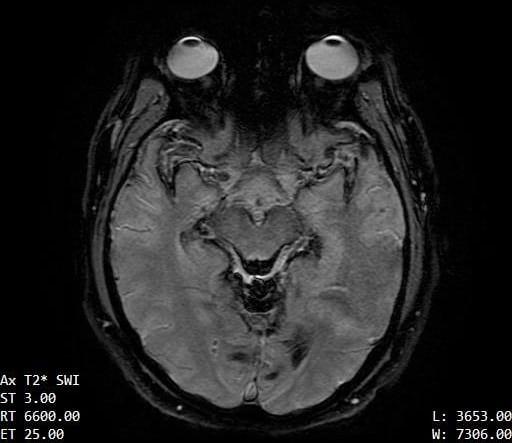

The contours of the cerebrum, cerebellum, and brainstem are outlined with a T2 hypointense signal with blooming on susceptibility weighted sequences, which is compatible with the clinical history of superficial siderosis. A majority of the T2 hypointense signal is present in the superior folia of the cerebellum but also seen coating the surfaces of the brainstem, the cortical surfaces along the Sylvian fissures, and the cortical surfaces of the paramedian sulci of the frontal and occipital lobes. Few subcortical and periventricular T2/FLAIR hyperintensities are present in both cerebral hemispheres.²

If you look at each image, you can see the dark areas where his hemosiderin deposits are. The radiologist will use the same machine and settings, so we should visually compare the new images with these for some positive change.³